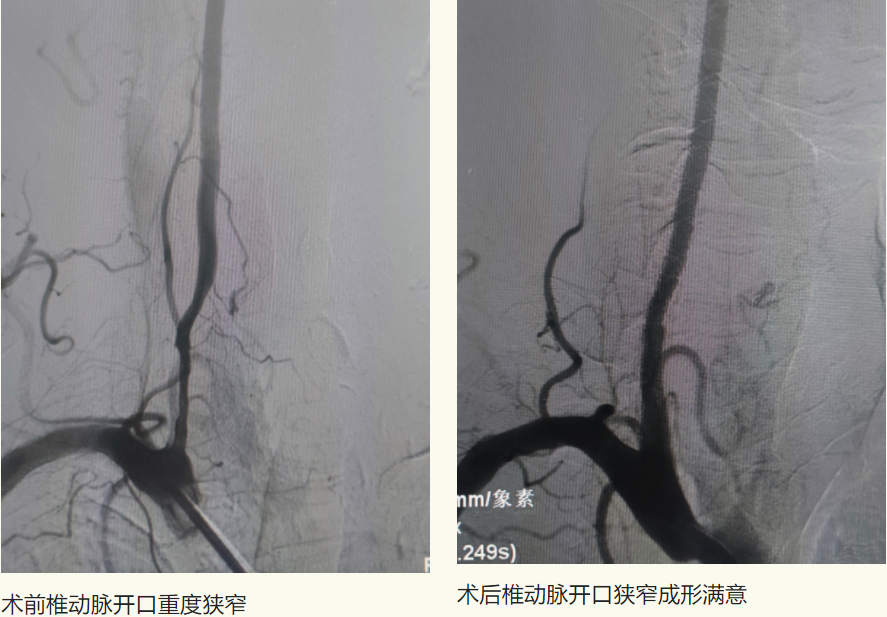

6月10日,家住富区74岁的李先生因“头晕伴行走不稳多年”,来到齐医附属一院就诊。行头CTA检查提示左侧锁骨下动脉管腔重度狭窄、双侧颈内动脉颅内段钙化斑块、管腔轻-中度狭窄、左侧大脑前动脉A1段重度狭窄。患者饱受疾病折磨,长年头晕给生活带来诸多不便,生活质量下降。以往此类患者需前往哈尔滨或者北京等著名医院进行介入手术治疗,大大增加了患者就医困难及经济负担。李先生经多方咨询,了解到刘忠锦副院长为神经介入专家,找到了附属一院刘忠锦副院长来完成治疗。

刘忠锦副院长经过仔细的问诊、查体后和家属详细的进行了沟通,患者选择相信附属一院的技术,决定住院进行手术治疗。入院后刘忠锦副院长带领神经介入团队及神经内五科医生认真地查房及阅片,经全脑血管造影诊断为左侧锁骨下动脉重度狭窄、锁骨下动脉盗血综合征,并制定了手术方案。

6月12日,经过完善的术前准备后,刘忠锦副院长带领神经介入团队为患者行锁骨下动脉支架植入术,术后支架形态良好,前向血流恢复,左侧椎动脉血流较手术前明显改善,且无并发症发生。